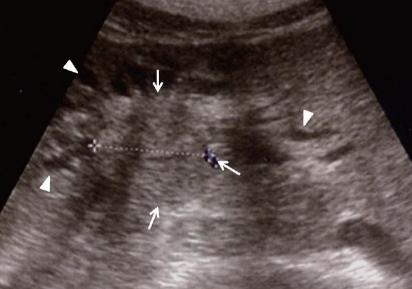

- проведение зондирования и исследования внутренних органов больного с помощью УЗИ;